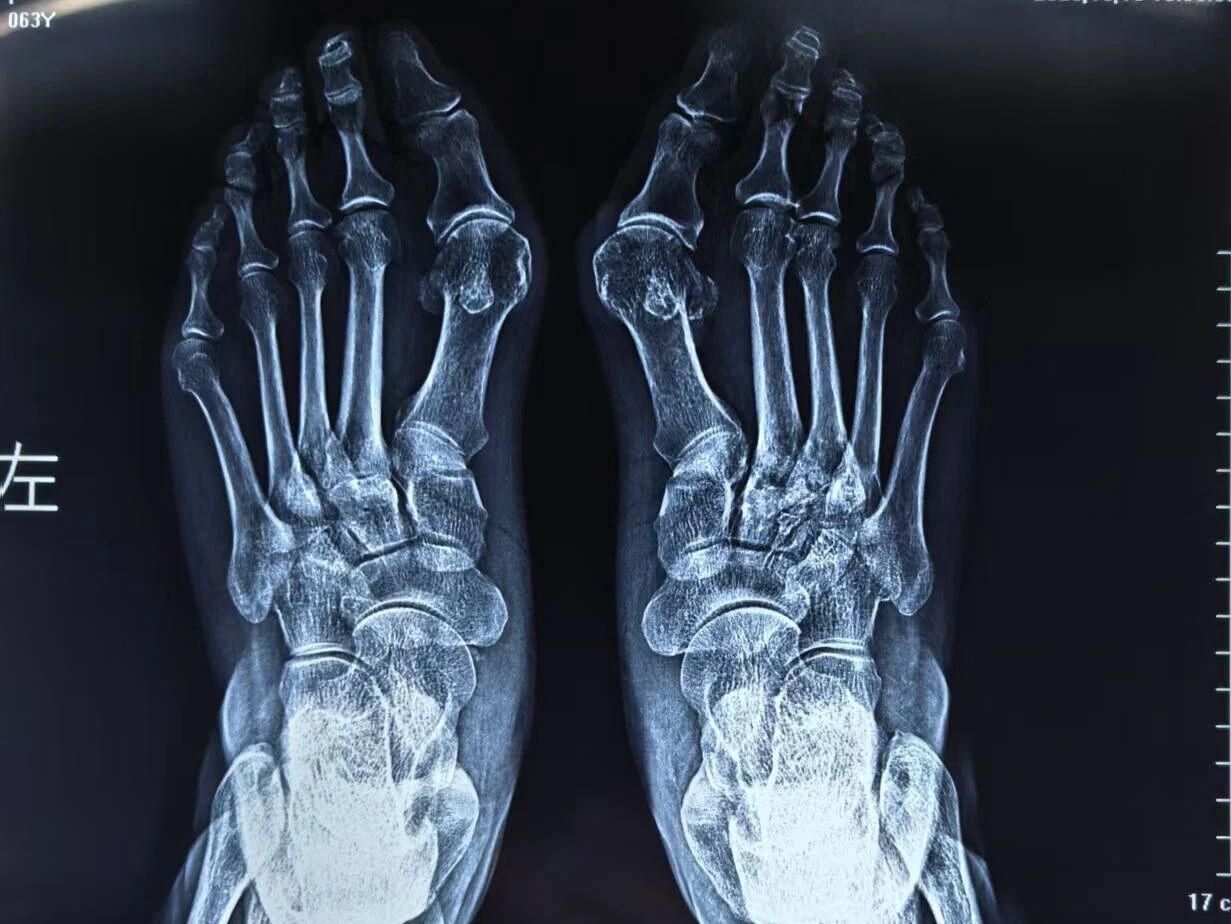

近日,周口人合医院迎来中国中医科学院广安门医院骨科徐颖鹏博士。作为国家级骨科大咖,徐博士此次专程为周口患者带来国际先进的微创诊疗方案,让群众在家门口即可享受顶级医疗技术。在当天的诊疗活动中,多名拇外翻患者成为首批受益者,徐博士采用局部麻醉,不到四分钟便完成单侧手术,创口仅如米粒大小,术后即可行走。 ▲徐颖鹏博士为多位患者行拇外翻微创手术 一位刚刚结束手术的患者惊喜地表示:“这十几年一直被脚变形和疼痛折磨,没想到在人合医院不到十分钟就彻底解决了!真是太神奇了!” ▲术前

▲术后

▲术前